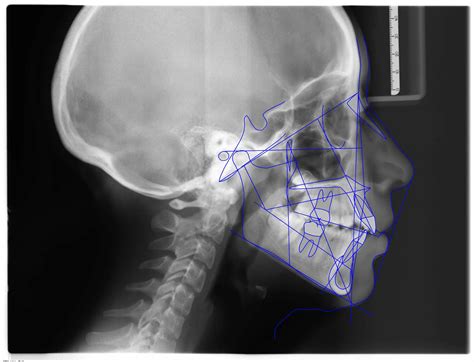

Figura 5 Telerradiografía lateral de cráneo pretratamiento.

La telerradiografía lateral de cráneo inicial (fig. 5) evidencia el resalte existente, con una mandíbula que presenta características típicas de tener un buen potencial de crecimiento.

Figura 6 Trazado cefalométrico pretratamiento.

Cefalométricamente, según Ricketts (fig. 6), encontramos un patrón mesofacial, con una maloclusión esquelética de Clase II de origen mandibular, con incisivos inferiores retroinclinados.